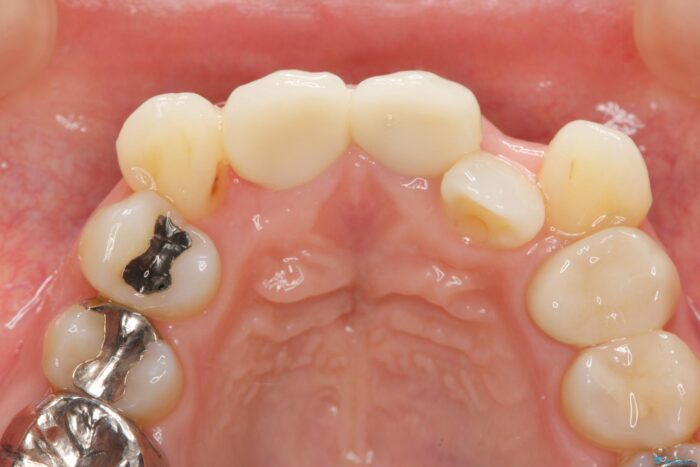

レントゲン検査の結果、以前の根管治療の詰め物が突き出た状態でしたので、まず精密な再治療を行います。同時に、歯磨きがしにくく虫歯の原因になっている右上側切歯を抜歯し、その後、セラミック治療で全体を美しく修復する計画です。

歯磨きがしにくい歯を抜歯することで、今後の虫歯の再発を防ぐ治療計画としました。